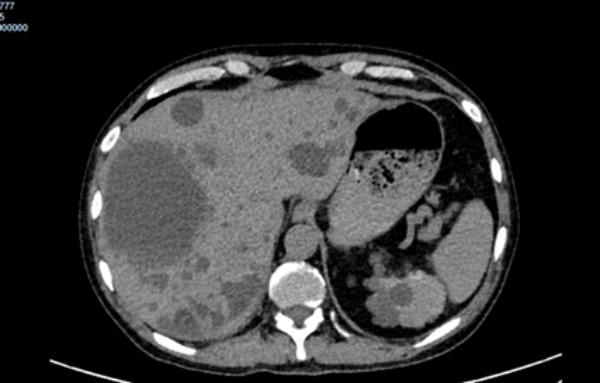

除了尿毒症,张先生还存在多囊肾、肾性贫血、肾性高血压、冠心病、电解质紊乱等多种基础疾病,身体早已是 "千疮百孔"。在外院治疗期间,尽管医生给予了积极的抗感染、退热等对症支持,但高热、寒战、右上腹剧痛等症状反复发作,病情持续恶化。外院告知尽快行肝囊肿穿刺引流术以控制感染,因多囊肝不同于普通肝脓肿,可能存在穿刺不成功、穿刺出血等并发症,患者及家属因担心手术风险,始终犹豫不决。

各学科专家迅速围绕患者病情展开深入分析:重症医学科指出,患者感染症状突出,需高度警惕脓毒症发生,尽早行肝囊肿穿刺引流是控制感染的关键,同时需严密监测内环境变化,保障透析治疗;超声科仔细评估后认为,在充分告知风险并获得患者及家属理解的前提下,可实施超声引导下肝囊肿穿刺引流术,精准定位能最大限度降低风险;普内科表示将全力保障患者规律透析,维持肾功能稳定;药学部结合患者慢性肾衰竭 5 期的特殊情况,建议根据病原学结果调整抗感染方案,兼顾药物安全性与有效性;肝胆科支持当前内科综合治疗策略,重点关注感染控制与肝功能保护。

突破心理壁垒,实施关键穿刺:穿刺引流是扭转病情的核心环节,但患者及家属仍对风险心存顾虑。董江川主任与超声科专家多次与患者及家属沟通,用通俗的语言解释病情的紧迫性、穿刺的必要性以及超声引导技术的精准性,最终赢得了他们的信任。6 月 30 日,超声引导下肝囊肿穿刺引流术顺利实施,当场引流出 200ml 黄色脓性液体。术后效果立竿见影 —— 患者当日下午即停止发热,腹痛显著缓解,精神状态明显好转。